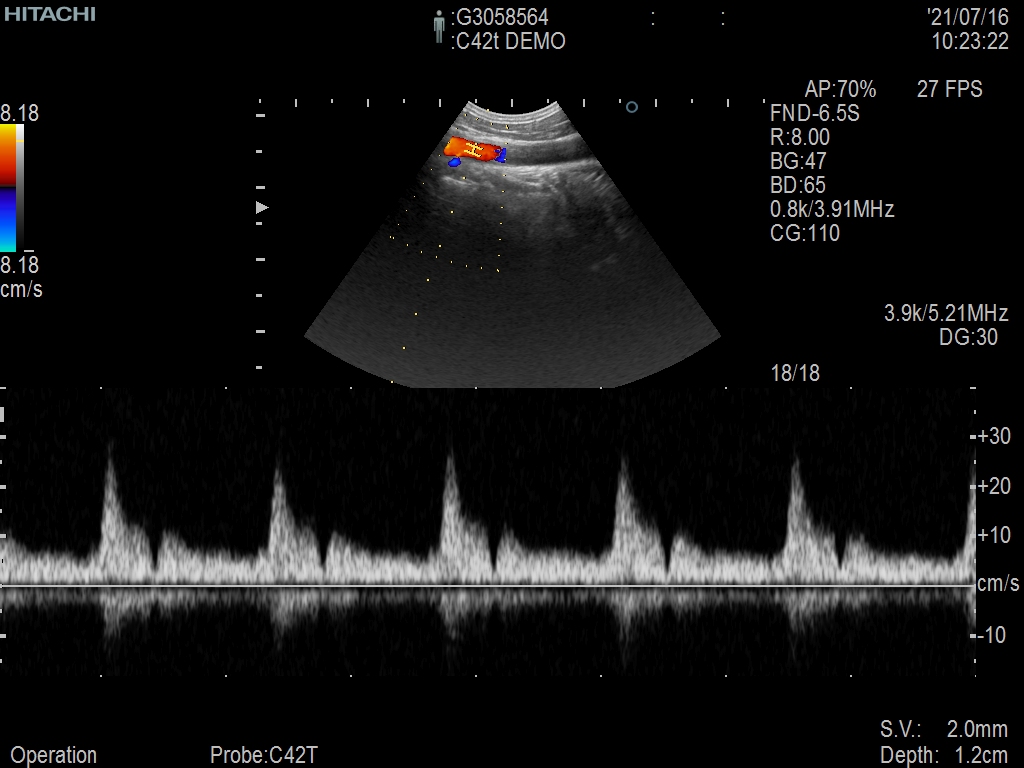

Hitachi C42T Ref Intraoperative Convex – ARIETTA

ARIETTA Convex C42T Intraoperative

Intended use

Intraoperative Finger-grip T-Style

Frequency Range

10 – 3 MHz

System compatibility

ARIETTA

Περιγραφή

Hitachi C42T Intraoperative Convex – ARIETTA

Frequency Range: 10 – 3 MHz

Scan Width: 20 mm Radius

Scan Angle: 65° FOV

Smart Connector

Hitachi C42T Intraoperative Convex – ARIETTA for Intraoperative Finger-grip Convex T-Style

Compatible with Hitachi Arietta Systems